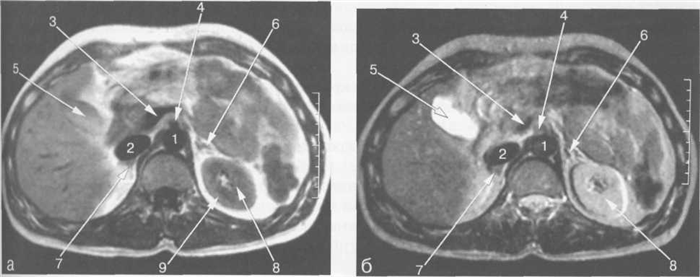

Рис. 11.11. МРТ брюшной полости в аксиальной плоскости на уровне печеночных вен.

1 — аорта; 2 — желудок; 3 — хвостатая доля печени; 4 — левая ветвь воротной вены; 5 — передние сегменты правой доли печени; 6 — задние сегменты правой доли печени; 7 — нижняя полая вена; 8 — правая печеночная вена; 9 — правая ветвь воротной вены; 10 — левая доля печени; 11 — селезенка; 12 — диафрагма.

Рис. 11.12. МРТ брюшной полости в аксиальной плоскости на уровне поджелудочной железы.

1 — аорта; 2 — нижняя полая вена; 3 — селезеночная вена; 4 — хвост поджелудочной железы; 5 — желудок; 6 — селезенка; 7 — толстая кишка; 8 — задние сегменты правой доли печени; 9 — задние сегменты ветви правой воротной вены; 10 — передние сегменты ветви правой воротной вены; 11 — медиальные сегменты левой доли печени; 12 — латеральные сегменты левой доли печени; 13 — левый надпочечник; 14 — верхний полюс левой почки.